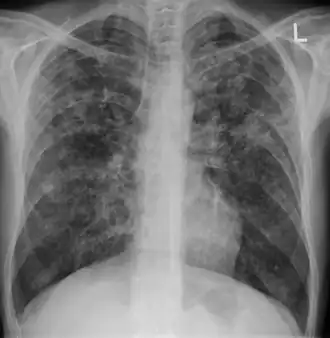

Chest X ray showing miliary tuberculosis

Miliary tuberculosis is a form of tuberculosis that is characterized by a wide dissemination into the human body and by the tiny size of the lesions (1–5 mm). Its name comes from a distinctive pattern seen on a chest radiograph of many tiny spots distributed throughout the lung fields with the appearance similar to millet seeds—thus the term "miliary" tuberculosis. Miliary TB may infect any number of organs, including the lungs, liver, and spleen.[2]

Testing for miliary tuberculosis is conducted in a similar manner as for other forms of tuberculosis, although a number of tests must be conducted on a patient to confirm diagnosis.[3] Tests include chest x-ray, sputum culture, bronchoscopy, open lung biopsy, head CT/MRI, blood cultures, fundoscopy, and electrocardiography.[9] The tuberculosis (TB) blood test, also called an Interferon Gamma Release Assay or IGRA, is a way to diagnose latent TB. A variety of neurological complications have been noted in miliary tuberculosis patients—tuberculous meningitis and cerebral tuberculomas being the most frequent. However, a majority of patients improve following antituberculous treatment. Rarely lymphangitic spread of lung cancer could mimic miliary pattern of tuberculosis on regular chest X-ray. [14]

A case of miliary tuberculosis in an 82-year-old woman: